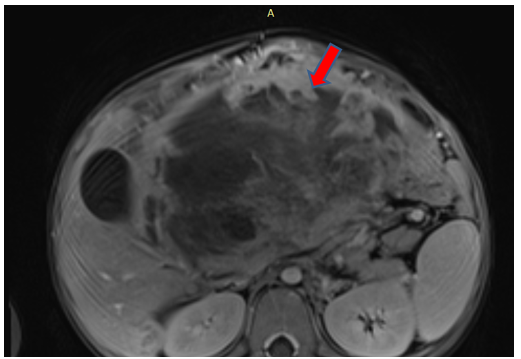

Intra-Abdominal Rhabdomyosarcoma in a Child: A Case Report

Sanae Jellal, Rayane Bekkaoui, Jihane El Houssni, Lina Belkouchi, Nazik Allali, Siham El Haddad and Latifa Chat. 7(9): 01-05.